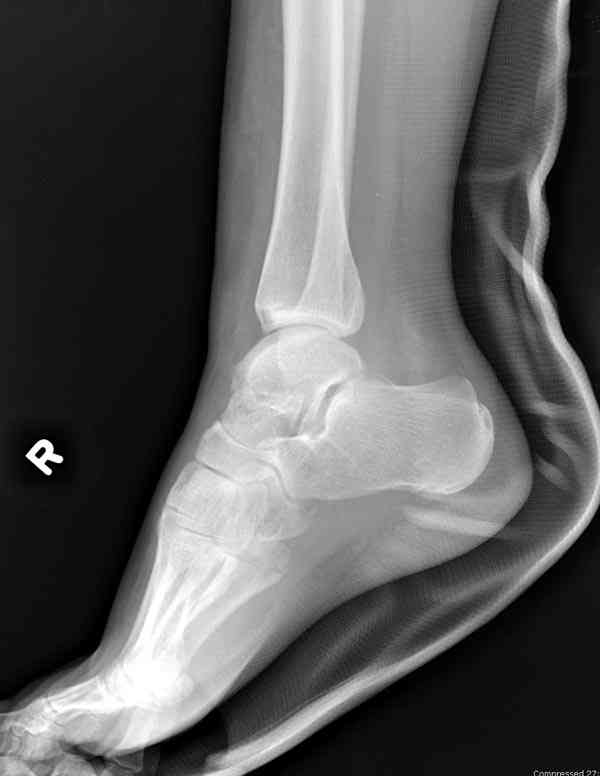

Interesting case

The ankle joint looks ruined. I wonder howcome is it as ruined after 2 days. I would open the joint( Some people would artroscope it) and judge the osteosynthes vs ankle fusion according to the ankle joint condition. The subtalar does not look injured, but if you feel there is a clinical

problem- CT it. Above all- when I see such an X-Ray I call the resident who ordered it and tell him that I would expect him first thing to reduce it on arrival since the soft tissue suffer and I hope that currently the p-nt is reduced to some extent at least.

а основании двух видов ренгенограмм невозможно радикально решить о необходимости открытой репозиции или первичного артродеза.

Для оценки состояния нужны дополнительные исследования, например Canale или Broden ренгенограммы и Компьютерная томография.

При переломах тарана всегда имеется риск AVN, а классификация Hawkins поможет разобраться с предполагаемыми осложнениями.

Если в первом типе, когда перелом шейки без смещения, тогда AVN менее 10%, при втором типе когда имеется смещение и вывих тарана в субталарном сочленении меньше 40%, а при типе III когда смещение в голеностопном и субталарном суставах - около 90% и в типе IV, когда происходит полный вывих, риск AVN достигает 100%.